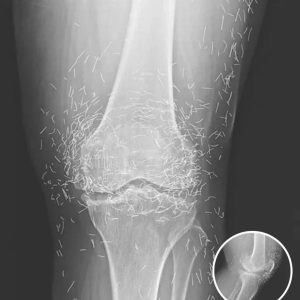

Doctors Stunned After Looking At This X-Ray Of Woman Suffering Joint Pain

A routine X-ray revealed a shocking surprise: hundreds of tiny gold needles embedded in the knees of a 65-year-old woman with severe joint pain. The woman, from…